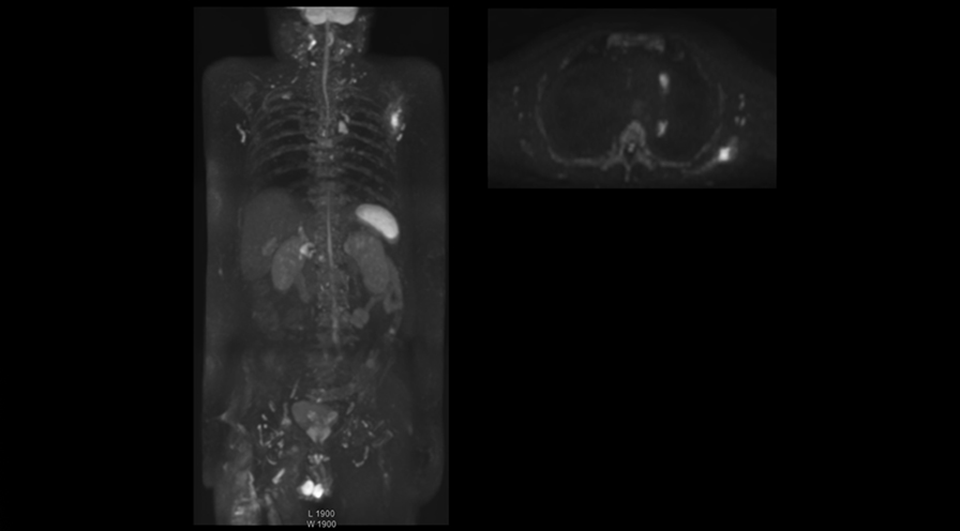

“When we limited the scan coverage to the area from neck to femur, we could fit more clinical information in approximately the same scan time. So, we added coronal mDIXON, sagittal T1-weighted, and sagittal STIR sequences to our examination, instead of performing only axial DWIBS and coronal single-shot TSE scans.”

The single shot T2-weighted TSE images are used for morphology and compared to DWIBS images to identify T2 shine-through. Sagittal STIR images are used in patients with inflammation or bone metastasis.

“With coronal DWIBS, we can perform a full whole body exam, including other sequences, within 30 min.”

“Switching to coronal DWIBS – rather than axial – further shortens scan time,” says Mr. Naka. “Important is that a dS SENSE factor of 5 shortens exam time while high image quality can be maintained, thanks to Ingenia’s dStream architecture.” He adds that the coronal orientation also avoids artifacts that are specific to combining axial images.

“When we use a coronal DWIBS acquisition, we can perform a full whole body examination, including other required sequences, within 30 minutes,” he says.

Kawasaki Sawai Hospital’s whole body protocol also includes an mDIXON FFE sequence. Because mDIXON provides images for four contrast types – water only, fat only, in-phase and out-of-phase – from a single acquisition, it is useful in many ways.

“mDIXON FFE allows us to quickly get information we need to assess the presence of fat. That gives us more information when we need to diagnose bone lesions, and when we are asked to judge fat-containing lesions such as hepatocellular or renal carcinoma,” Dr. Nobusawa says.

“The mDIXON fat images can help us to differentiate fatty bone marrow from bone lesions. This is especially useful in elderly people, who tend to have fattier bone marrow. The water images provide a high signal-to-noise ratio in the intestinal canal, which is valuable for visualizing lesions in the colon,” he says.